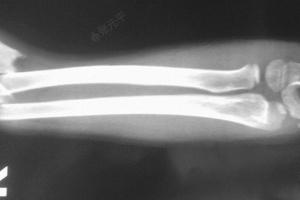

手腕三角骨撕脱性骨折

手腕三角骨撕脱性骨折,手腕三角骨骨折

手腕三角骨骨折

手腕三角骨骨折图片

三角骨骨折